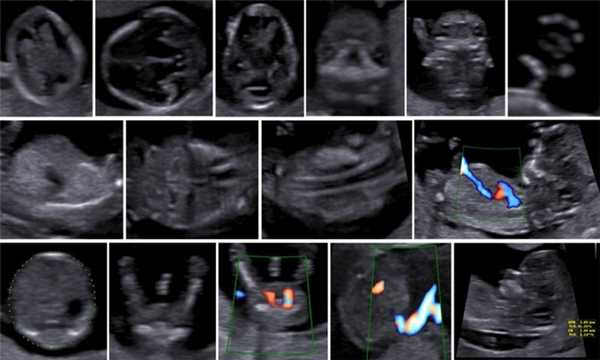

Описанные в литературе величины частоты выявления дефектов в I триместре беременности значительно различаются в зависимости от изученных популяций, методов и периодов [5]. По мере развития методов ультразвуковой диагностики усовершенствовался и анатомический анализ для I триместра беременности. Международное общество по применению УЗИ в акушерстве и гинекологии (International Society of Ultrasound in Obs tetrics and Gynecology - ISUOG) в 2013 г. предложило руководство для клинической практики, предполагающее проведение оценки анатомии плода между 11 нед 0 дней и 13 нед 6 дней беременности (рис. 3) [6].

Революцией в пренатальной ультразвуковой диагностике явилось появление объемной эхографии, которая, обладая такими качествами, как неинвазивность, безопасность и возможность многократного применения у одной пациентки, имеет высокую информативность в исследовании анатомии плода и изучении его фенотипа. При применении различных режимов объемной эхографии абсолютно очевидно их преимущество по сравнению с обычным сканированием. Детально можно изучить лицо плода (рис. 1-4) в различные сроки беременности, начиная со сроков первого пренатального скрининга в 11-14 нед, конечности плода, причем не только их наличие и положение (рис. 5, 6), но и состояние и количество пальцев (рис. 7-9) как на руках, так и на ногах. Также можно изучить позвонки плода (рис. 10), состояние твердого нёба (рис. 11, 12), строение наружного уха (ушной раковины) (рис. 13), состояние основных швов черепа и родничков, исключая их преждевременное закрытие при кранисиностозах (рис. 14, 15).